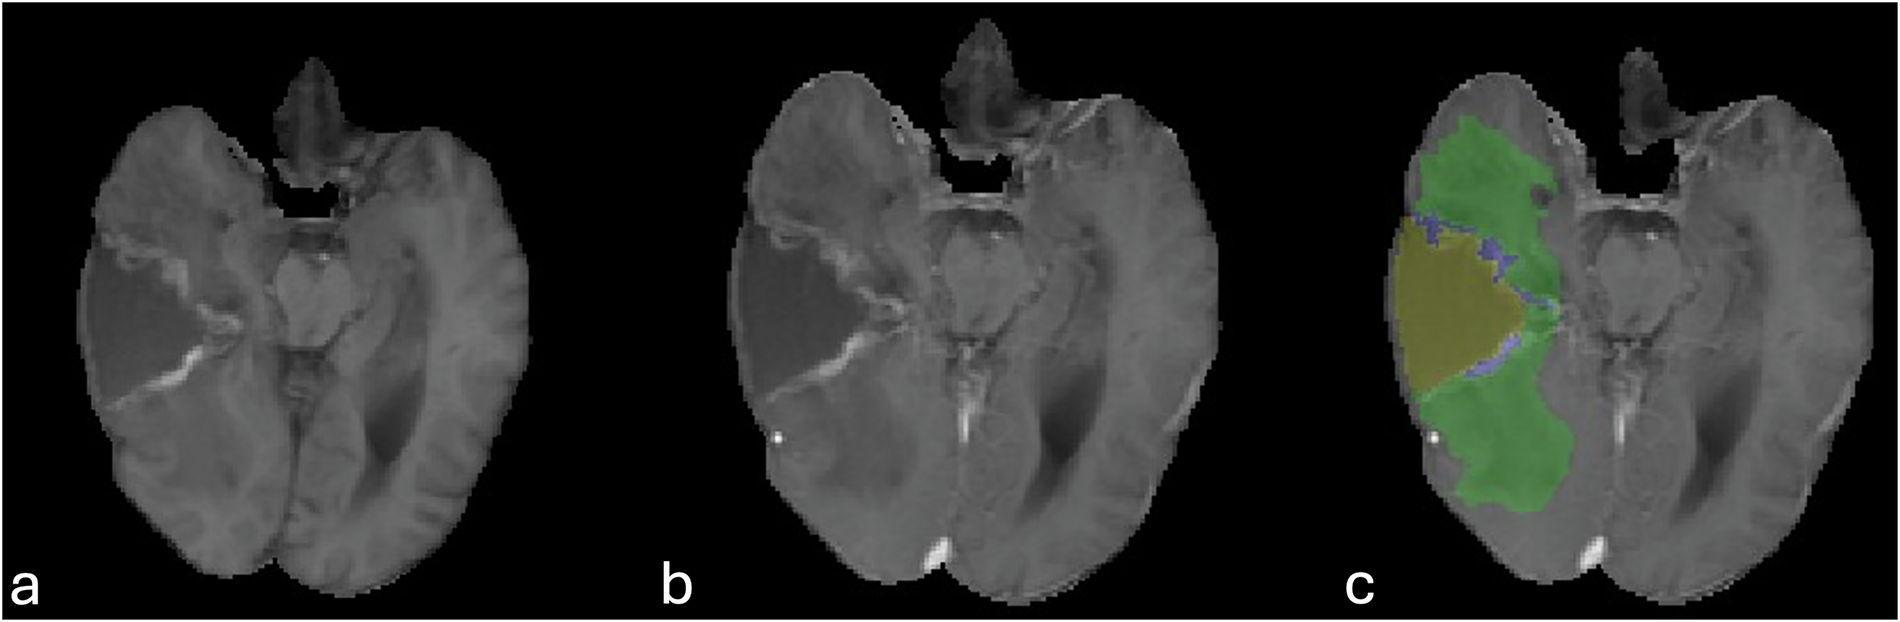

Fig. 5

Misclassification of the T1 shortening of the resection cavity rim as enhancing tumor label. Peripheral T1 hyperintensity of the anteromedial and posteromedial margins of the resection cavity (a), without change in T1 following IV gadolinium-based contrast administration (b). Note wrong assignment of the enhancing tumor label (blue, c).